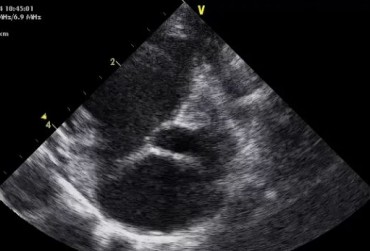

Badanie echokardiograficzne projekcja lewostronna koniuszkowa czterojamowa 2

19 lutego 2019

Urszula Bartoszuk